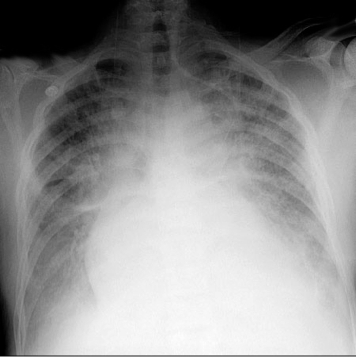

(Image: Kerly B lines)

Kerley B Lines